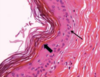

Give one diagnosis for this case:

A

Histology shows multinucleated giant cells

A: central giant cell granuloma